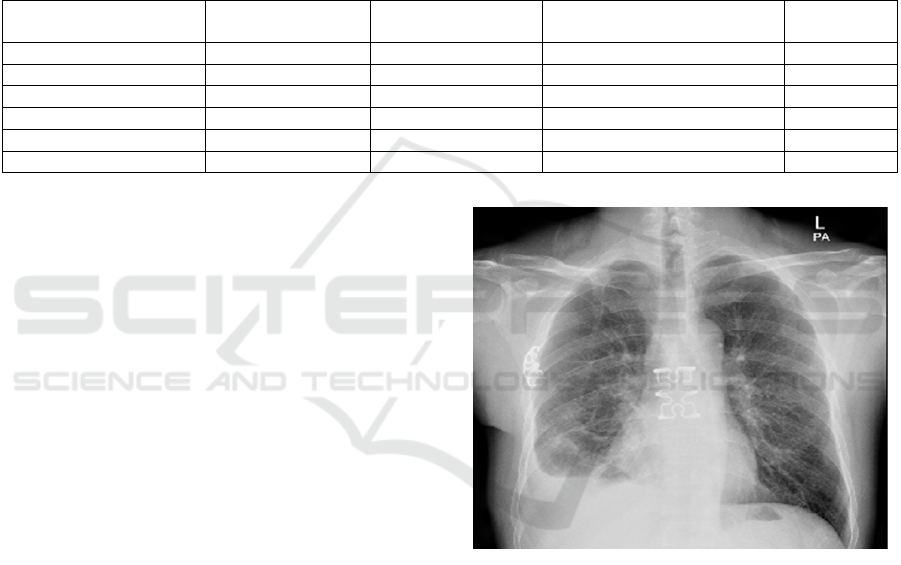

experiment can be done. In this paper, take the

photo. The photo is shown in Figure 2.

Figure 2: X-ray Chest Picture. (Youlai Doctor, 2024)

Ask the question Does this patient have steel

nails in his chest, reply in Chinese. Under the

repetition penalty parameter 1.2, the model

recognizes a steel nail in the patient's chest and adds

that it may be a tool for fixing the chest wall during

treatment or surgery; under parameter 1.5, the

previous output remains unchanged, but the sentence

X-ray shows L-1023 is fictionalized at the end.

If the model is not prompted, but is simply asked,

Do you know what is wrong with this patient?, the

model assumes that the patient has small nodules and

masses in the lungs.

This experiment illustrates a number of points.

One is that the repetition penalty parameter 1.5 would

fudge the content and is not suited to the rigors of the

medical field; the other is that the model's image

parsing is so powerful that it is able to identify foreign

objects in the chest cavity on monochrome X-rays,

even though it requires some prompting to

identifythem as steel nails, which only shows that the

model has not been trained in the medical field. What

is certain is that lightweight models have unlimited

potential for future deployment in various domains.